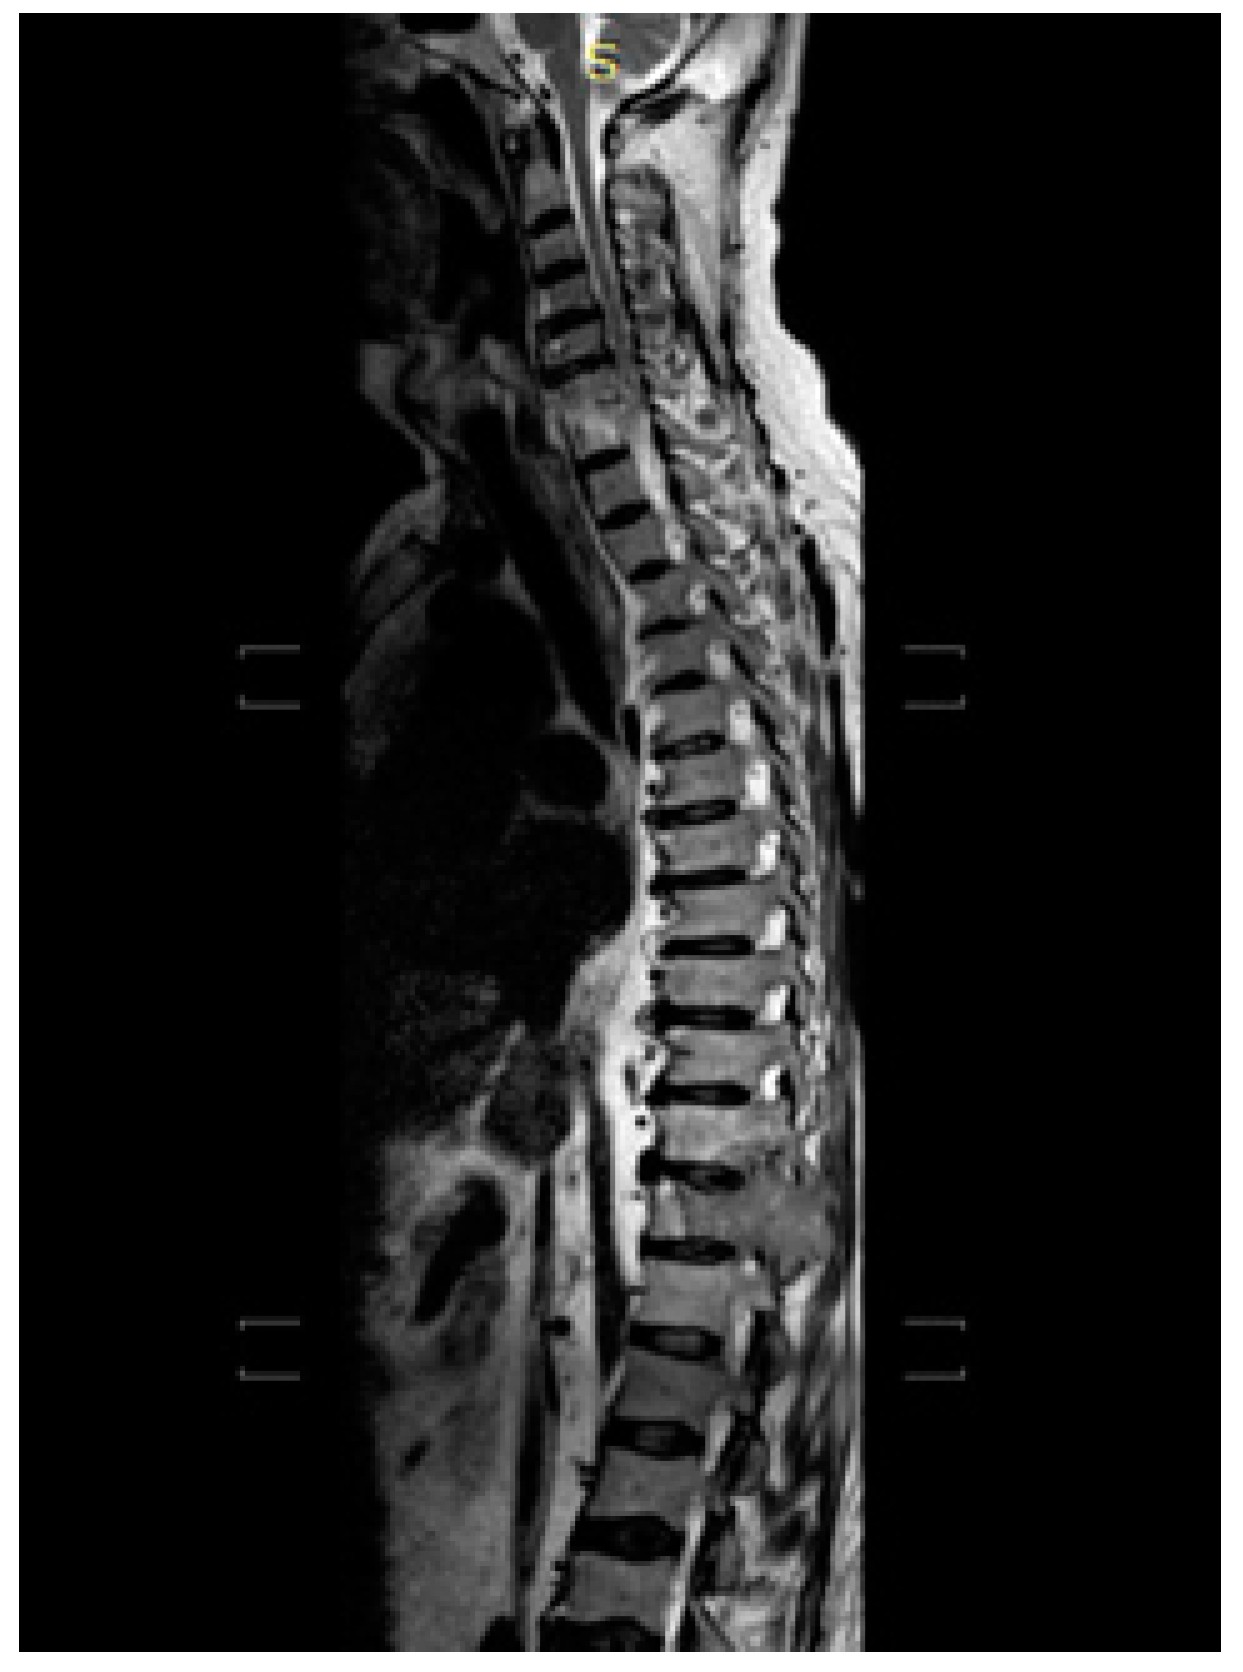

2. Case Description